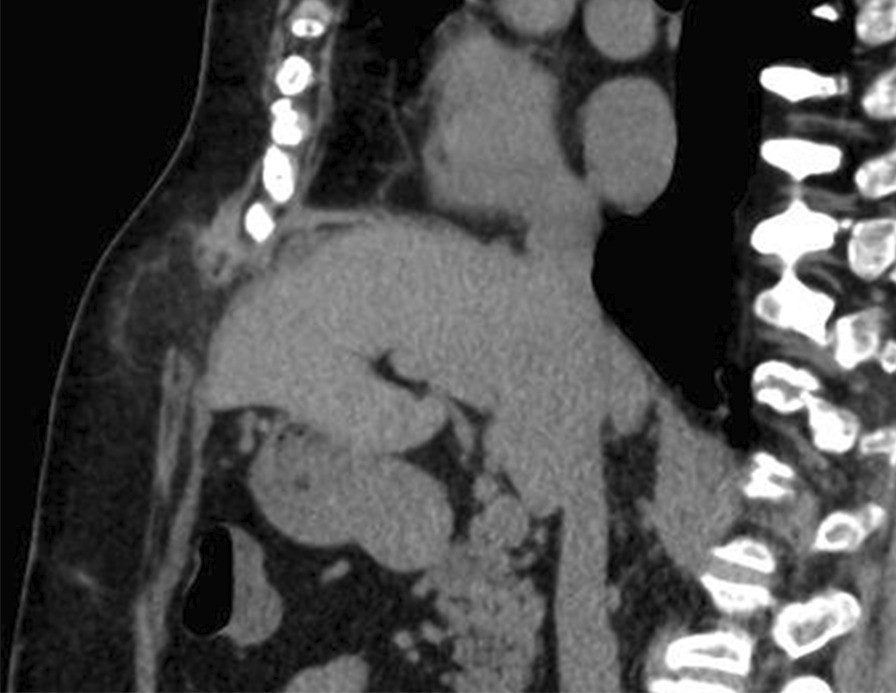

Fig. 4

Abdominal computed tomography after 6 months. No recurrence has been observed